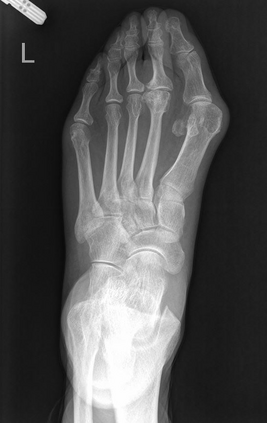

Angular measurements is essential to make a resonable treatment for Hallux valgus (HV), a common forefoot deformity. However, it still depends on manual labeling and measurement, which is time-consuming and sometimes unreliable. Automating this process is a thing of concern. However, it lack of dataset and the keypoints based method which made a great success in pose estimation is not suitable for this field.To solve the problems, we made a dataset and developed an algorithm based on deep learning and linear regression. It shows great fitting ability to the ground truth.